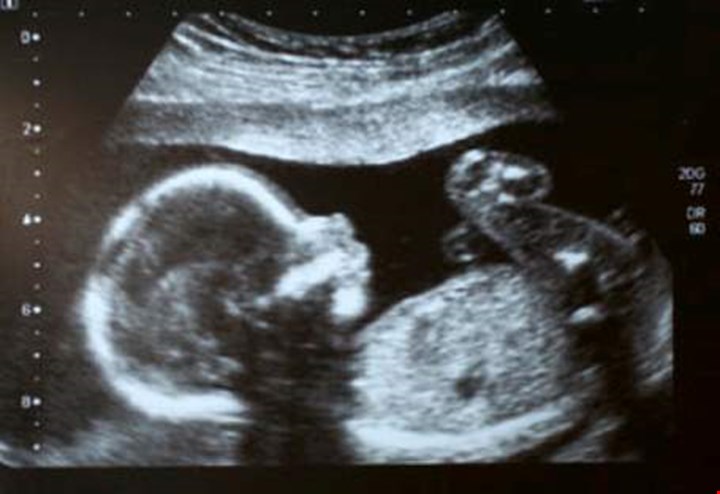

• Et offentlig tilbud om tidlig ultralyd. Svangerskapsomsorgen skal gi ekstra oppfølging til foreldre, og sørge for god informasjon om tilbudet før foreldrene velger det. Dersom ultralyd avdekker avvik skal ekstra svangerskapsomsorg gis.

• Et offentlig tilbud om tidlig ultralyd. Svangerskapsomsorgen skal gi ekstra oppfølging til foreldre, og sørge for god informasjon om tilbudet før foreldrene

• ikke innføre rutinetilbud om tidlig ultralyd til alle friske gravide, men sikre at dagens retningslinjer for tilgang til tidlig ultralyd blir praktisert likt over hele landet

• Avvise offentlig finansiering av tidlig ultralyd i uke 11-13 til alle gravide, så lenge det er lite dokumentasjon for en helsemessig gevinst.

• at ultralyd i uke 11-12 ikke skal regnes som en del av svangerskapsomsorgen, da en slik ultralyd først og fremst er egnet til å oppdage avvik som kan lede til abort.

• gå imot innføring av tidlig ultralyd (uke 11-13) til alle (screening).

• ikke å innføre et offentlig tilbud om tidlig ultralyd til alle gravide i tillegg til dagens tilbud, så lenge det ikke er dokumentert positiv helsegevinst forbarnet eller moren

• Det bør være mulig å benytte preimplantasjonsdiagnostikk og fosterdiagnostikk, og ultralyd skal kunne brukes også før 12 svangerskapsuke der dette er ønsket og faglig forsvarlig.